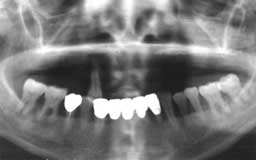

Hさん 初診時 53歳 男性

50歳頃まではもう少し歯があったそうですが、歯科医院に行くたびに「歯槽膿漏です」といわ れて抜歯。60歳まで何とか総入れ歯にしたくないという

Hさん 19年後 72歳

上顎の補綴処置と左下の親知らずを抜歯。歯槽膿漏の手術を行うことなく月に1度の歯石除去 を継続して行った結果、初診時から大きく変化することなく19年を経過しました